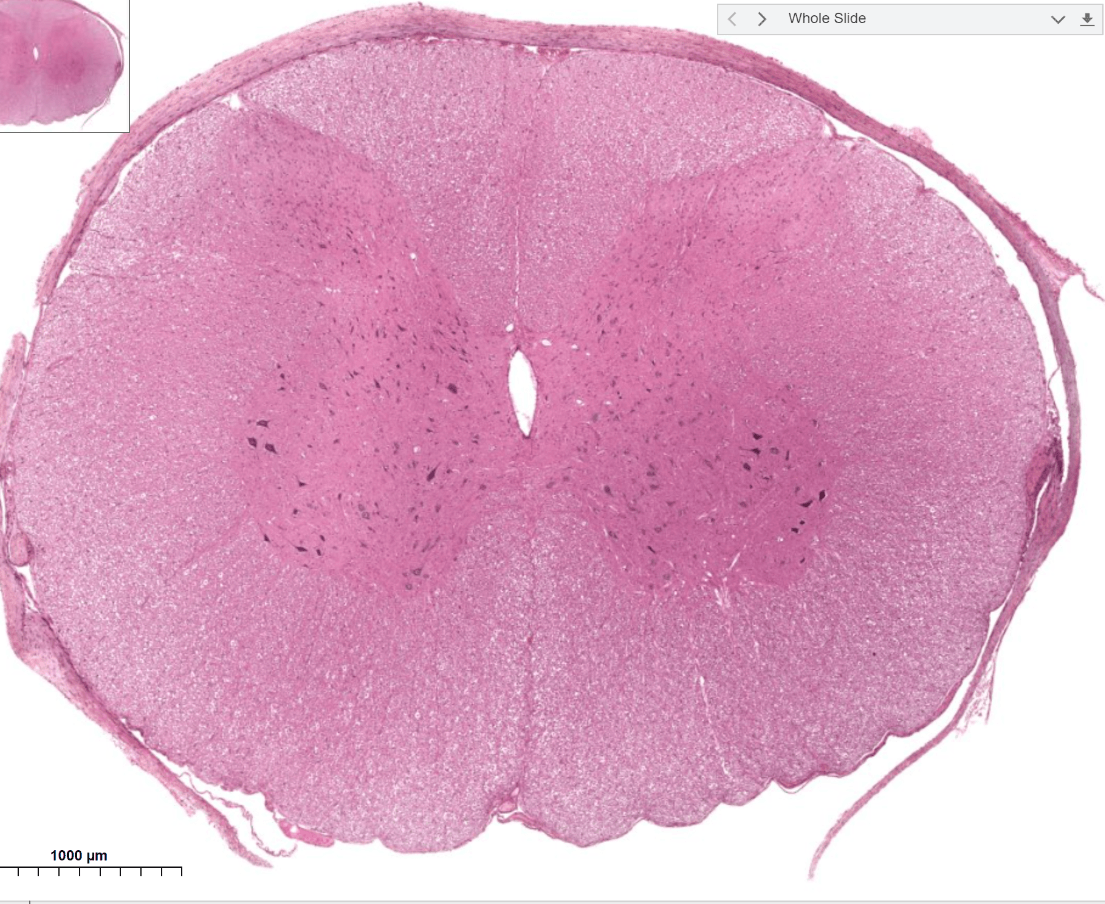

Spinal cord